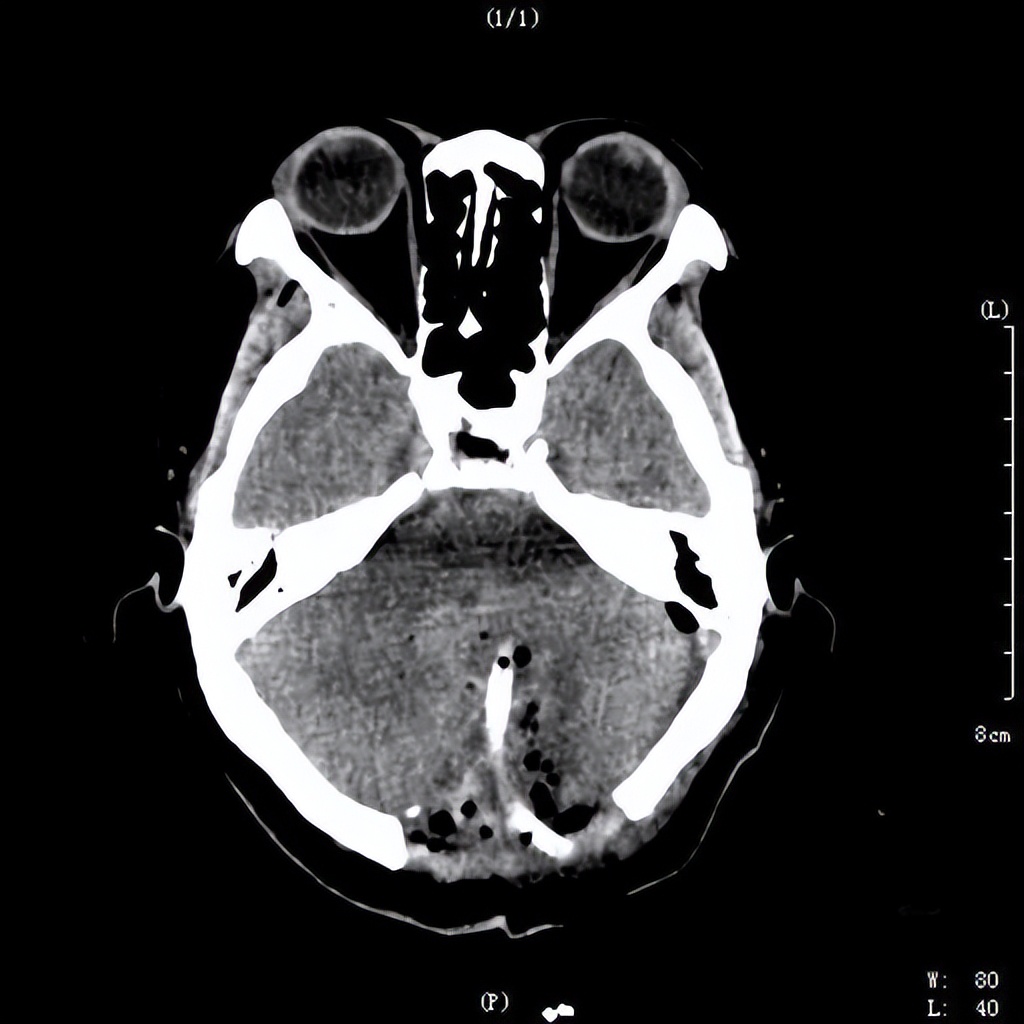

术前检查显示小脑出血破入脑室,挤压脑干